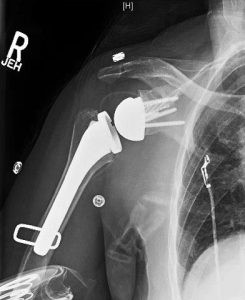

CASE 2

This is a similar case of posterior superior wear, but with a slightly smaller vault. There is 15 to 20 degrees of retroversion and 10 degrees of superior inclination. It should be noted that there is a posterior osteophyte that I didn’t want to use as support for the implant. As in the previous case, the goal is to place the implant while removing as little bone as possible and maintaining as much of the cage as possible in the vault. To avoid reaming the subchondral bone, the posterior superior augment baseplate was used. I under corrected the version to 8 degrees and moved the center point slightly anterior to avoid the posterior osteophyte. This left the slightly longer cage of the posterior/superior augment barely penetrating the anterior cortex which is of little to no consequence. As in case 1, in the absence of preoperative planning and GPS, finding a proper starting point on the glenoid face to place the implant in the appropriate amount of acceptable retroversion, avoiding the posterior osteophyte, and reaming minimal to no subchondral bone would be extremely difficult.